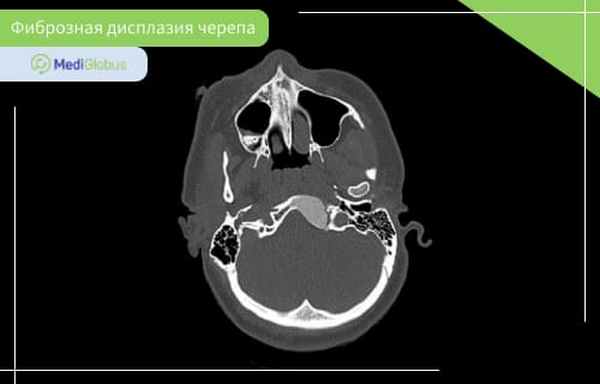

Фиброзная дисплазия костей черепа

Фиброзная дисплазия костей черепа встречается в 10-25% монооссальной формы болезни, и 50% – полиоссальной.

Чаще всего этот вид фиброзной дисплазии поражает переднюю часть черепа: лобную, клиновидную, решетчатую кость, верхнюю или нижнюю челюсть. Фиброзная дисплазия основания черепа встречается очень редко.

Симптомы фиброзной дисплазии черепа зависит от расположения образования. Болезнь может проявиться через заложенность носа, кривые зубы, асимметрию лица, выступающий лоб, выпученные или неправильно расположенные глаза. В некоторых случаях может быть деформация черепа. Степень поражения отличается от пациента к пациенту.

Диагностика фиброзной дисплазии костей черепа включает КТ, МРТ и рентген. Кроме этого, пациенту может понадобиться консультация невролога, челюстно-лицевого хирурга и стоматолога.